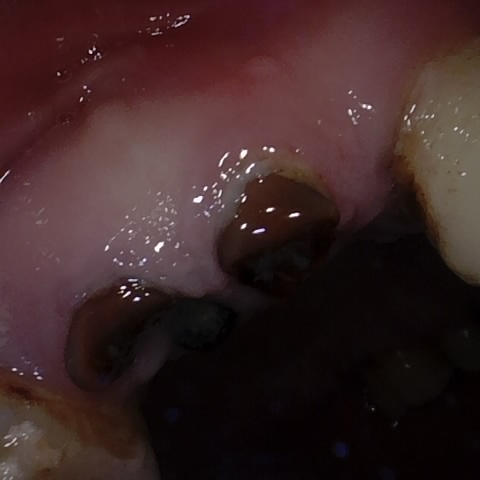

Annotated as "Good"